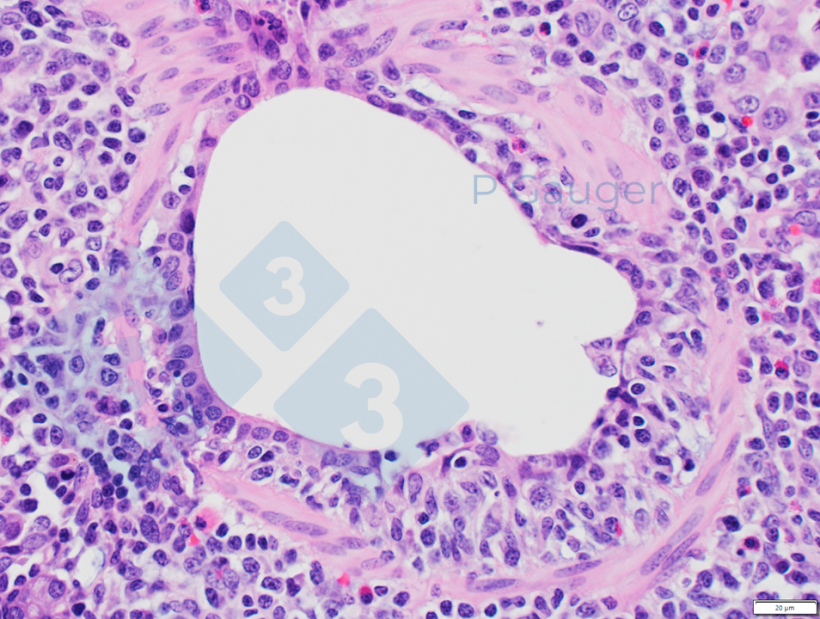

Figure 4 : Histopathologie du poumon montrant un amincissement de l'épithélium bronchiolaire, ce qui est un exemple de nécrose (Source photo : Phil Gauger ISUVDL).